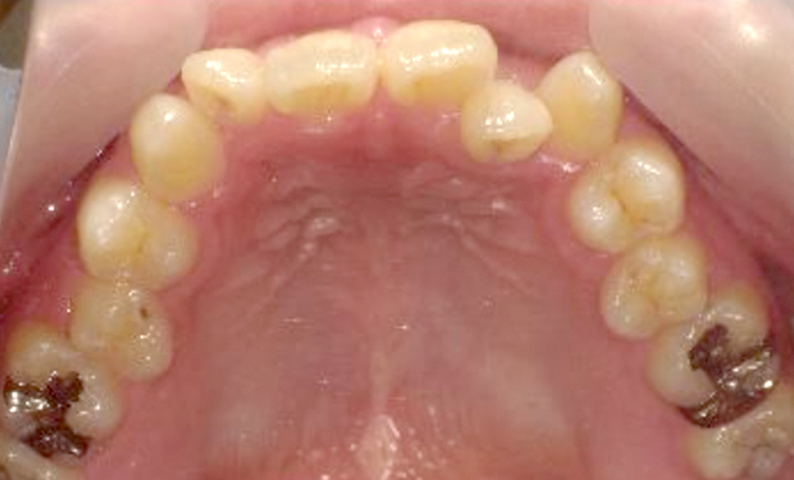

症例_008 上顎だけの部分矯正

治療期間:6ヶ月金額:27万円+税女性前歯のガタガタ上の前歯だけ